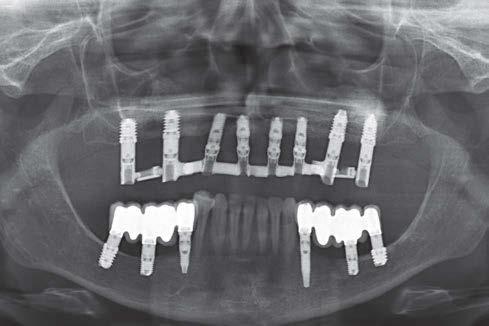

Elevación de seno transcrestal con implantes cortos versus elevación de seno convencional con ventana lateral

Estudio retrospectivo comparativo a boca partida

Ya que ambas técnicas quirúrgicas siguen hoy en día en pleno auge, aunque las indicaciones para cada una de ellas han evolucionado en el tiempo, quedando la elevación convencional únicamente indicada hoy en día en aquellos casos de 1-2 mm de volumen óseo residual (donde es muy complejo estabilizar un implante corto por elevación transcrestal), creemos útil poder comparar la evolución de ambos procedimientos en el tiempo, a ser posible en un mismo paciente, donde el resto de variables que puedan afectar al seguimiento sean iguales, y, por lo tanto, la comparación sea más útil. Por ello, hemos realizado un análisis retrospectivo de pacientes en los que se han realizado los dos procedimientos, uno en cada cuadrante superior y ver la evolución en el tiempo de los implantes insertados en cada caso. Con esta idea en mente, hemos llevado a cabo un estudio retrospectivo que evaluase estos factores, y que se detallan a continuación.

MATERIAL Y MÉTODO

Fueron reclutados de forma retrospectiva pacientes en los que se hubiesen realizado ambas

técnicas de abordaje de seno maxilar: elevación convencional o la inserción de implantes cortos y extra-cortos mediante elevación transcrestal, desde enero de 2010 en adelante. Todos los pacientes fueron estudiados antes de la inserción de los implantes mediante modelos diagnósticos, exploración intraoral y realización de un TAC dental (Conebeam) analizado posteriormente mediante un software específico (BTI-Scan II).